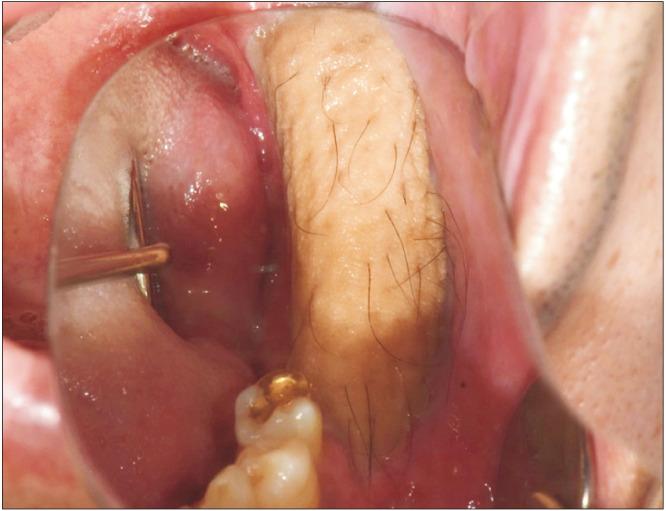

Primary intraosseous squamous cell carcinoma (PIOSCC) is very rare type of squamous cell carcinoma (SCC) that occurs within the jaw and arises from remnants of odontogenic epithelium with no connection to the oral mucosa. This study reports two cases of PIOSCC of the mandible. Reported in this article are two cases of PIOSCC of the mandible that were treated with resection and reconstruction using a fibular free flap. The first case was a 36-year-old male patient who complained of right mandibular pain. Computed tomography (CT) and panoramic radiograph revealed a large radiolucency in the mandibular ramus area. At first, an odontogenic keratocyst was tentatively diagnosed, and an excision procedure was carried out at another clinic. A final biopsy after cyst enucleation revealed well-differentiated SCC, so we proceeded with segmental mandibulectomy and reconstruction using a fibular free flap. The second case was a 48-year-old male patient with left mandibular pain. CT and panoramic radiograph revealed irregular radiolucency in the mandibular angle area near tooth #38. At first, osteomyelitis was tentatively diagnosed, and a curettage was carried out. A later biopsy revealed well-differentiated SCC, so segmental mandibulectomy and reconstruction with a fibular free flap were secondarily performed. Our two cases have had no recurrence. The facial appearance of both patients is satisfactory, and the neo-mandibular body created using a fibular bone transfer displays adequate bony volume.

原发性骨内鳞状细胞癌(PIOSCC)是一种非常罕见的鳞状细胞癌(SCC),发生于颌骨内,起源于牙源性上皮残余,与口腔黏膜无连接。本研究报告了两例下颌骨PIOSCC病例。本文报道了两例下颌骨PIOSCC病例,采用游离腓骨瓣进行切除和重建治疗。第一例是一名36岁男性患者,主诉右下颌疼痛。计算机断层扫描(CT)和全景X线片显示下颌支区域有一个大的透射区。起初,初步诊断为牙源性角化囊肿,并在另一家诊所进行了切除手术。囊肿摘除后的最终活检显示为高分化SCC,因此我们进行了下颌骨节段性切除并用游离腓骨瓣进行重建。第二例是一名48岁男性患者,有左下颌疼痛。CT和全景X线片显示38号牙附近下颌角区域有不规则透射区。起初,初步诊断为骨髓炎,并进行了刮除术。后来的活检显示为高分化SCC,因此二期进行了下颌骨节段性切除并用游离腓骨瓣进行重建。我们的两例病例均无复发。两名患者的面部外观均令人满意,使用腓骨骨移植构建的新下颌体显示出足够的骨量。